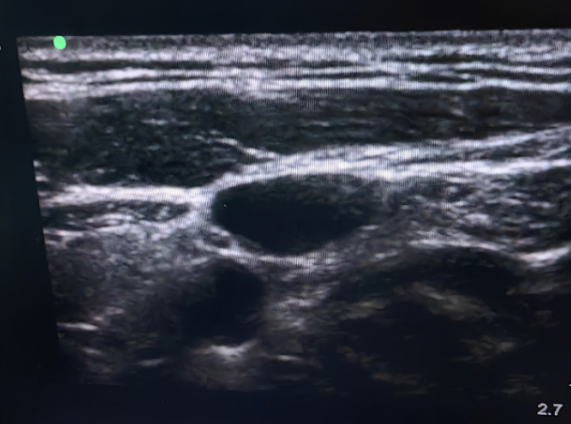

▲超声未见左侧颈内静脉

▲超声引导右侧颈内静脉穿刺

手术伊始,团队计划采用左侧颈内静脉穿刺建立通路,却多次尝试均未成功。面对这一突发状况,团队并未停滞,随即联合超声医学科展开紧急协作。通过精准的超声影像学评估,手术团队明确了左侧颈内静脉缺失的解剖事实,果断调整策略,于右侧颈内静脉成功建立手术入路,为手术推进扫清了第一道障碍。